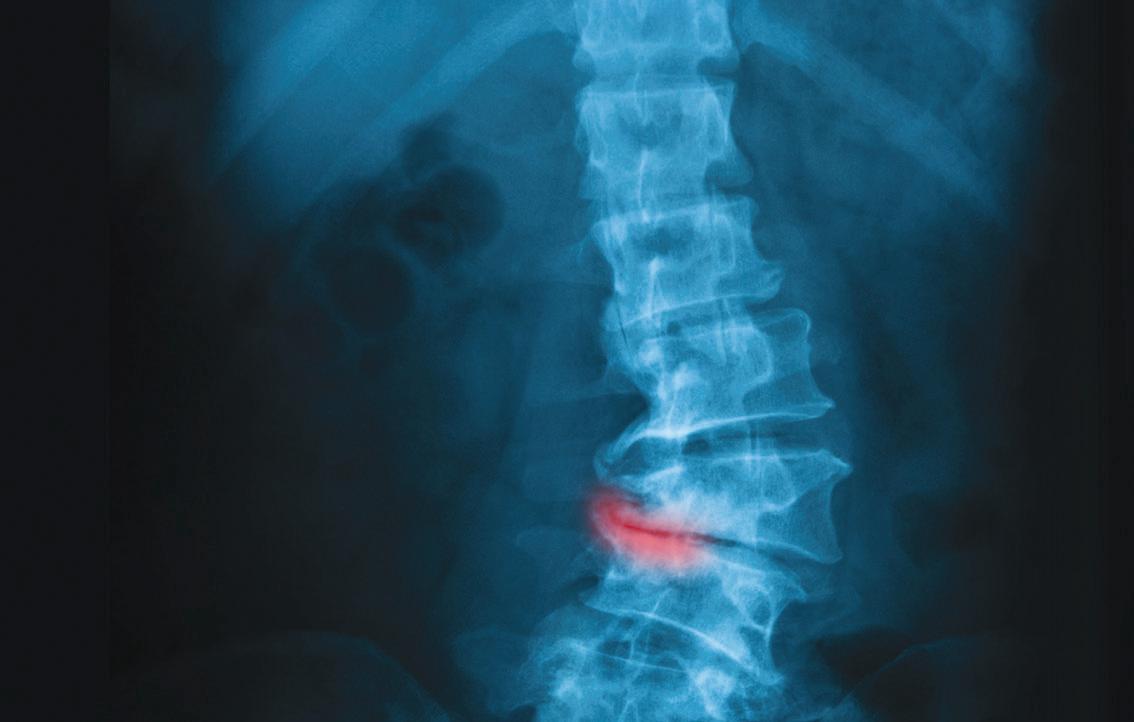

ANSWER: Yes, PCSK9 inhibitors are very effective at lowering cholesterol and reducing the risk of heart attacks in high-risk people. Because these drugs are given by injection and are quite expensive, they are not usually the firstline treatments. We have decades of experience using statins, so they remain the first choice for most.

However, if a person cannot take a statin, or one of the alternatives such as bempedoic acid, then PCSK9i drugs are a very reasonable choice. In people with familial high cholesterol and extraordinarily high levels of cholesterol, combination therapy with two or three drugs (a statin, a PCSK9i and sometimes ezetimibe) is frequently used.